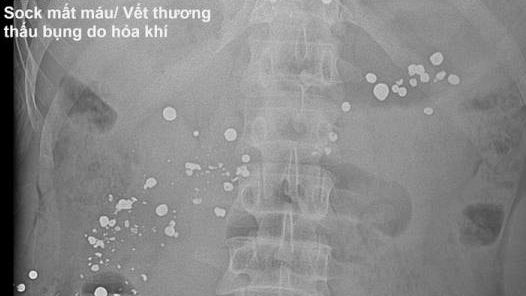

Cứu sống bệnh nhân bị súng tự chế bắn thủng dạ dày

Y tế 24h -  30/10/2019

Ảnh minh họa Theo đó, tối ngày 28-10, Bệnh viện Đa khoa Hùng Vương tiếp nhận nam bệnh nhân tên K, (39 tuổi, trú tại Tuyên Quang), trong tìn...